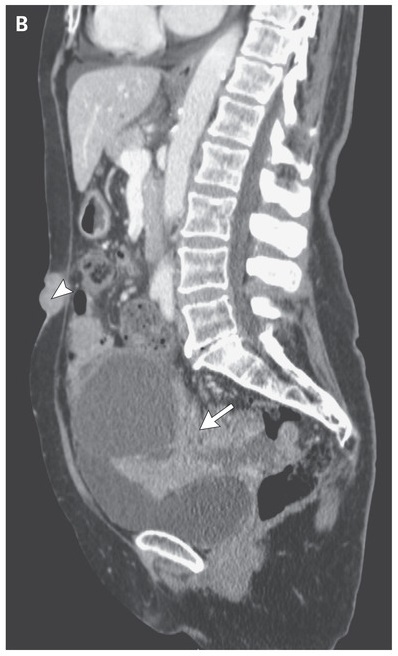

Computed tomography of the abdomen and pelvis showed a heterogeneous pelvic mass measuring 11 cm by 11 cm by 9.5 cm (arrow), moderate ascites, peritoneal carcinomatosis, and a nodule measuring 2.4 cm (largest diameter) in the umbilical region (arrowhead).

Diagnostic laparoscopy and biopsies of the large mass, umbilical nodule, and peritoneal implants were performed, and pathological analysis confirmed the diagnosis of high-grade serous ovarian carcinoma.

A Sister Mary Joseph’s nodule is a metastatic umbilical lesion in the umbilicus and is typically associated with gynecologic and gastrointestinal cancers. The patient underwent cytoreductive surgery and received adjuvant chemotherapy.